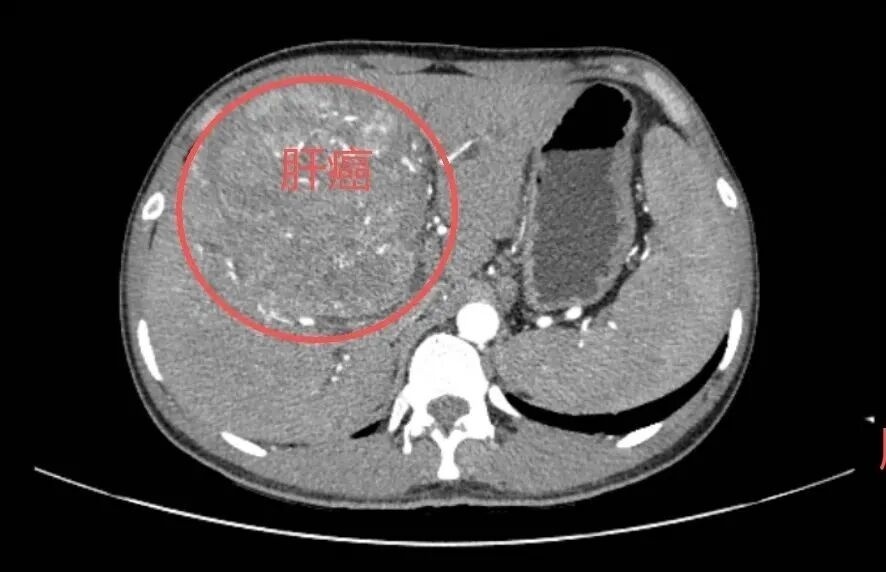

近日,东莞市滨海湾中心医院收治了一名25岁的肝癌晚期患者小王(化名)

图片

图片来源:东莞市滨海湾中心医院

令人惋惜的是小王10年前体检就查出乙肝表面抗原阳性却因年轻不当回事,从未规律复查、咨询专科医生,直至近期乏力、腹胀才就医,却已确诊肝癌晚期。